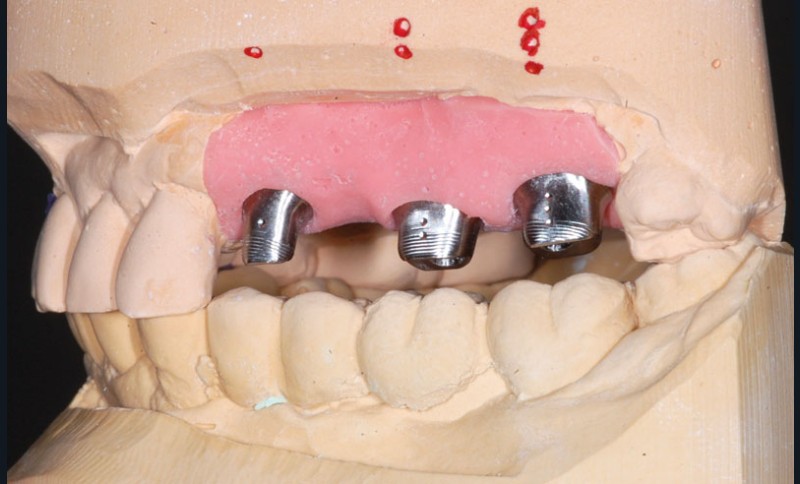

Le modèle de travail est fabriqué au laboratoire, des piliers CFAO Atlantis™ sont réalisés en fonction du bridge antagoniste transitoire.

Le modèle de travail est fabriqué au laboratoire, des piliers CFAO Atlantis™ sont réalisés en fonction du bridge antagoniste transitoire.

Le bridge 24-26 céramométallique et la couronne unitaire sur 27 sont réalisés. Les piliers CFAO sont transvissés sur les implants, puis les éléments céramo-métalliques sont posés. Le résultat montre un parfait respect du projet prothétique en fonction de la courbe occlusale obtenue avec le bridge transitoire réalisé avec le ProtempTM 4 et une adaptation parfaite.

Le bridge 24-26 céramométallique et la couronne unitaire sur 27 sont réalisés. Les piliers CFAO sont transvissés sur les implants, puis les éléments céramo-métalliques sont posés. Le résultat montre un parfait respect du projet prothétique en fonction de la courbe occlusale obtenue avec le bridge transitoire réalisé avec le ProtempTM 4 et une adaptation parfaite.

Le bridge 24-26 céramométallique et la couronne unitaire sur 27 sont réalisés. Les piliers CFAO sont transvissés sur les implants, puis les éléments céramo-métalliques sont posés. Le résultat montre un parfait respect du projet prothétique en fonction de la courbe occlusale obtenue avec le bridge transitoire réalisé avec le ProtempTM 4 et une adaptation parfaite.

Le bridge 24-26 céramométallique et la couronne unitaire sur 27 sont réalisés. Les piliers CFAO sont transvissés sur les implants, puis les éléments céramo-métalliques sont posés. Le résultat montre un parfait respect du projet prothétique en fonction de la courbe occlusale obtenue avec le bridge transitoire réalisé avec le ProtempTM 4 et une adaptation parfaite.

Le bridge 24-26 céramométallique et la couronne unitaire sur 27 sont réalisés. Les piliers CFAO sont transvissés sur les implants, puis les éléments céramo-métalliques sont posés. Le résultat montre un parfait respect du projet prothétique en fonction de la courbe occlusale obtenue avec le bridge transitoire réalisé avec le ProtempTM 4 et une adaptation parfaite.